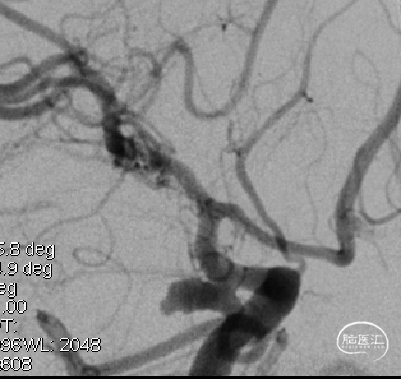

支架辅助WEB治疗不规则动脉瘤(国内首例)

微导丝辅助WEB治疗复发侧壁动脉瘤(国内首例)